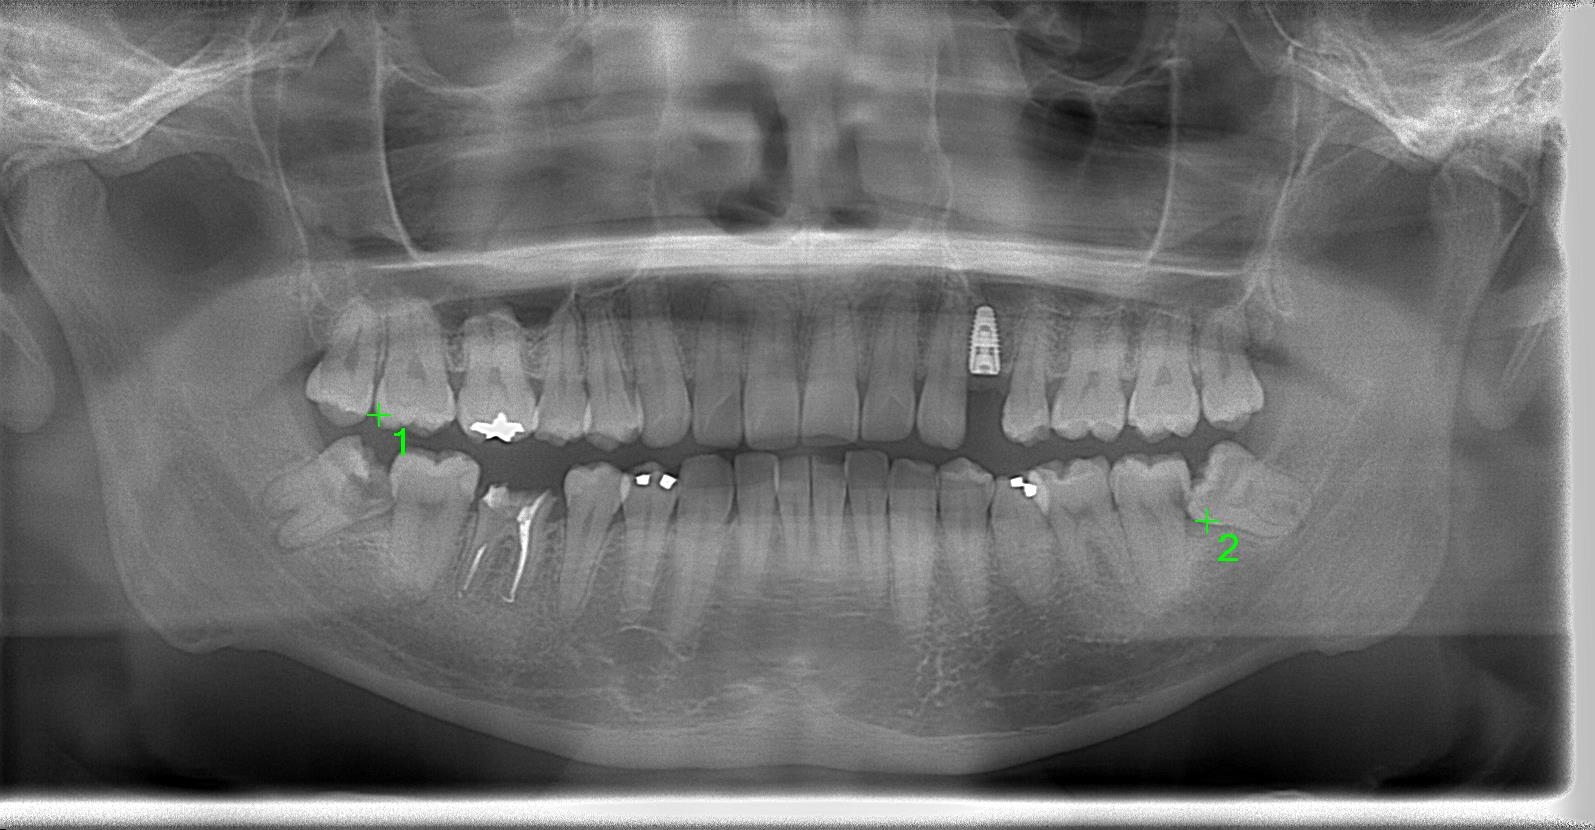

インプラント体1次埋入の術後パノラマレントゲン写真

術中インプラント埋入した状態は良好です。(左上)